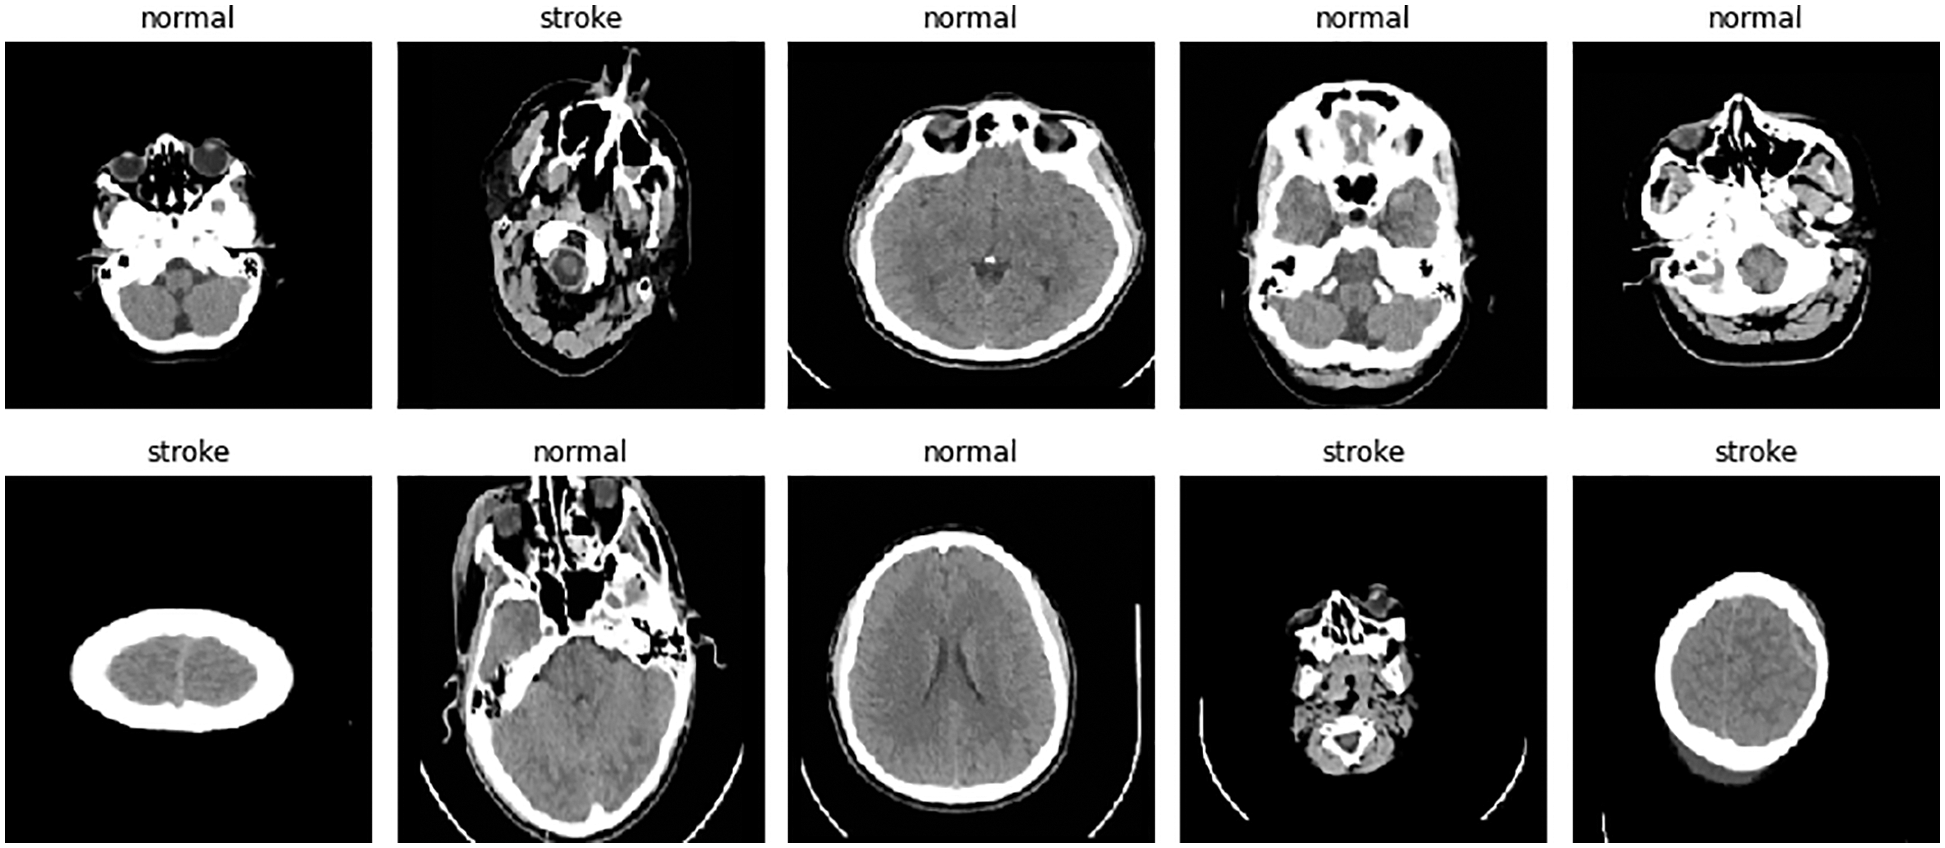

The aim of this study is to classify brain images in jpg or png format, where two classes are distinguished: stroke or healthy. The publicly available Kaggle platform was used as the dataset [42]. This dataset was divided into three 80%/20% groups (train, validation, and test) and contained 993 healthy images and 610 stroke cases for the training category; 240 healthy images and 146 stroke cases; and 313 healthy images and 189 stroke cases for test. The images in the data set were as shown in Fig. 3.

Figure 3: Contents of the dataset